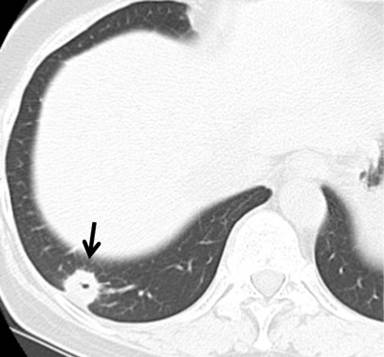

Chest CT before lung metastasis resection revealed a 1.5 cm, nodular shadow with spicular in the right lung segment 10 (Figure 2).

|

Figure 2. Chest CT before lung resection revealed a 1.5 cm, nodular opacity with spicula in the right lung segment 10 (arrow head). |